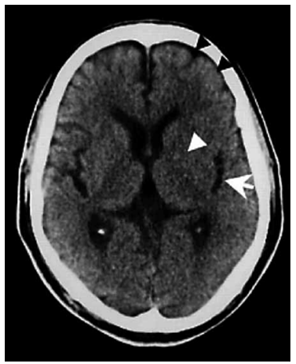

Paciente do sexo feminino, de 71 anos, portadora de hipertensão arterial e dislipidemia, em uso irregular das medicações, apresenta início súbito de hemiplegia direita e afasia há 170 min. Chega ao pronto atendimento apresentando no exame físico: PA: 190 x 100 mmHg; FC: 92 bpm; FR: 20 irpm; SatO₂: 95%; NIHSS: 14 pontos. Encaminhada para tomografia de crânio, que apresentou a imagem a seguir:

Enunciado 4925926-1

(Arquivo pessoal; imagem usada com autorização)

Qual é a conduta imediata?